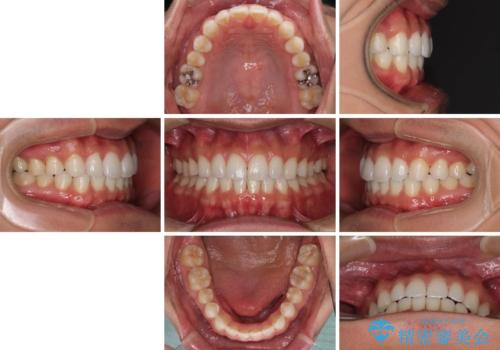

- 上下前歯のデコボコを気にして来院された患者様です。

以前矯正をした後戻りということで、歯列不正はそれほど大きくなかったため、インビザライン・ライトを用いて矯正治療を行うこととしました。

1日22時間以上しっかりと装着してくださったので、半年かからずに治療を終えることができました。